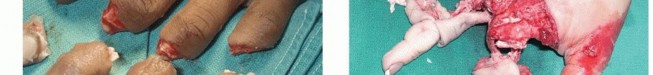

The mechanism of injury has a considerable effect on the potential for replantation. Sharp amputations are ideal for replantation because of the narrow zone of injury.The degree of tissue injury increases substantially with crush and avulsion mechanisms and may prohibit successful replantation (FIG 1).Most digit amputations occur as an isolated injury. When amputations occur in the multiply injured patient, consideration of other systemic injuries and adherence to advanced trauma life support (ATLS) protocols may prevent replantation.

FIG 1 • A. This hand sustained sharp amputation of the digits from a table saw. The narrow zone of injury made the digits ideal for replantation. B. This hand sustained a crush injury. The resultant wide zone of injury prohibited successful replantation. Expected survival rates of replanted digits are 80% or higher, with even higher survival rates in revascularized digits.